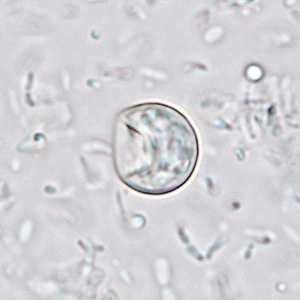

November - 2008 - Case #239

A 50-year-old man went to his health care provider after a week of intermittent diarrhea, cramps and nausea. Stool specimens were collected over three consecutive days and sent to the local public health laboratory for routine ova and parasite (O&P) work-up.